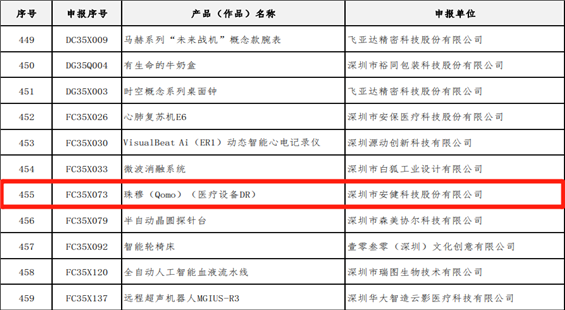

移动床边摄影进入百微新时代 388vip太阳集团科技发布国内首台大尺寸百微移动X光机(DR)

388vip太阳集团科技最新一代移动DR—飞燕Ⅱ,是国内首款大尺寸100微米超高清成像移动DR设备,具有1800万像素的超高分辨率,让床旁摄影的影像质量全面迈入高清时代。图像质量不仅远超当前市场上的移动DR设备,也远超过当前大部分固定DR设备的图像质量。

相较于普通DR的百万摄影像素,近2000万的高清像素,可以极大的提升床旁检查效率,包括骨科、新生儿科、心脏外科、重症监护科、急诊科等患者的快速检查。相较于目前市面上的低像素移动DR设备,100微米平板移动DR,在图像的分辨率、宽容度上都全面优于常规的130微米左右的移动DR设备。